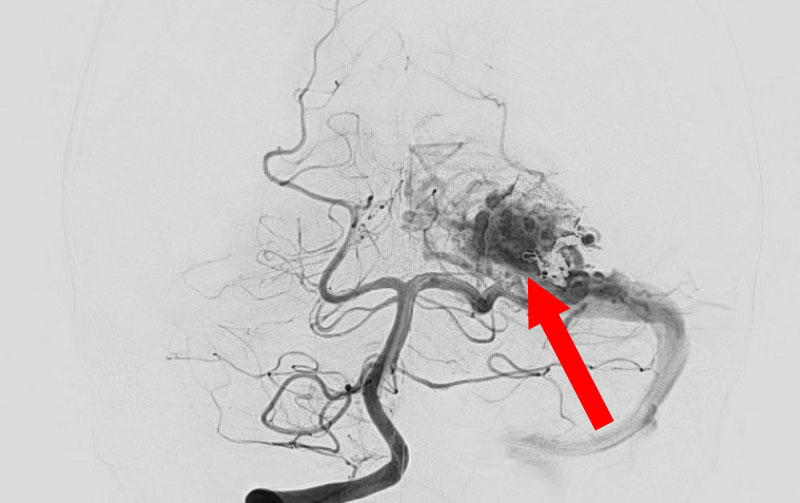

No.1592 手術前

No.1592 手術中